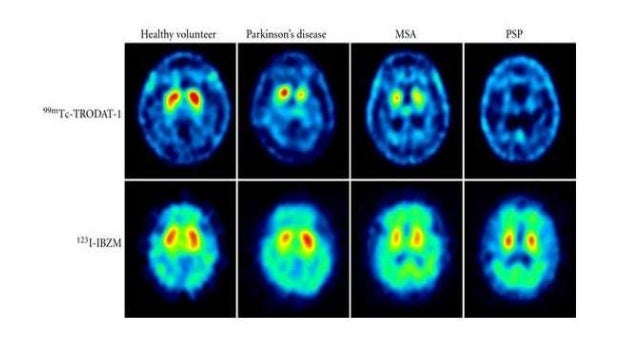

Tracers used for spect imaging of pd patients are presented in table 1.